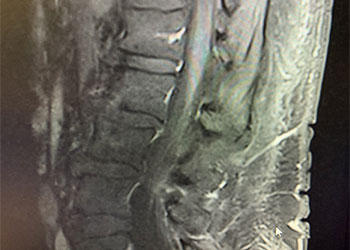

Back:

Revision Surgery Treats Intractable Neck Pain & Cervical Deformity

Author: Benjamin R. Cohen M.D., F.A.A.N.S., F.A.C.S., Read More!